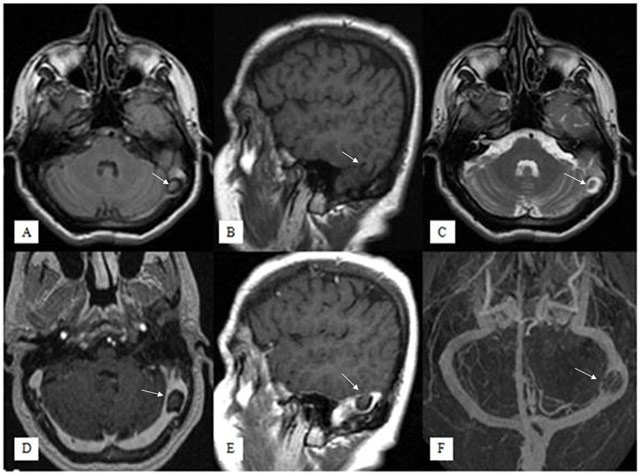

Figure 1

Fluid Attenuated Inversion Recovery axial (A), T1-weighted sagittal (B), T2-weighted axial (C), contrast-enhanced T1-weighted axial (D) and sagittal (E) images show a small herniation of temporal lobe parenchyma with surrounding CSF into left transverse sinus, that was isointense to brain parenchyma on all sequences (arrows). No pathological enhancement is seen but the brain herniation sac is causing moderate stenosis in the left transverse sinus. On venography imaging (F), there was left transverse sinus stenosis but no venous thrombosis.